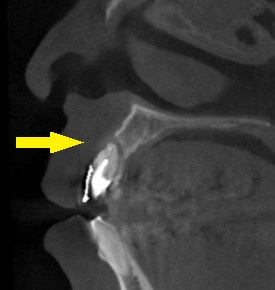

レントゲン写真、CTを撮ってみると、下の写真、中段のように歯根の先まで、骨が吸収されてしまっていました。